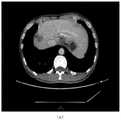

图9是本发明实施例提供的肝脏病灶图像处理方法采用两阶段病灶识别和独立病灶识别融合技术,识别肝脏内部和边缘病灶系统展示结果示意图。FIG. 9 is a schematic diagram showing results of a system for identifying internal and peripheral lesions of the liver using the two-stage lesion identification and independent lesion identification fusion technology provided by the liver lesion image processing method according to the embodiment of the present invention.

实施例三,两阶段病灶识别和独立病灶识别融合技术的肝占位识别效果。系统应用效果,如图9所示,两阶段病灶识别方法在肝脏分割的基础上识别病灶,可以非常准确的识别肝脏内部病灶,但是容易遗漏肝脏边沿病灶;独立病灶识别可以识别超出肝脏分割区域以外的边界病灶,融合这两个算法对于各类情形的肝占位识别效果非常显著。Embodiment 3: The liver mass recognition effect of the fusion technology of two-stage lesion recognition and independent lesion recognition. The application effect of the system is shown in Figure 9. The two-stage lesion identification method identifies lesions on the basis of liver segmentation, which can identify lesions within the liver very accurately, but it is easy to miss the border lesions of the liver; independent lesion identification can identify beyond the liver segmentation area. The fusion of these two algorithms has a very significant effect on the identification of liver mass in various situations.